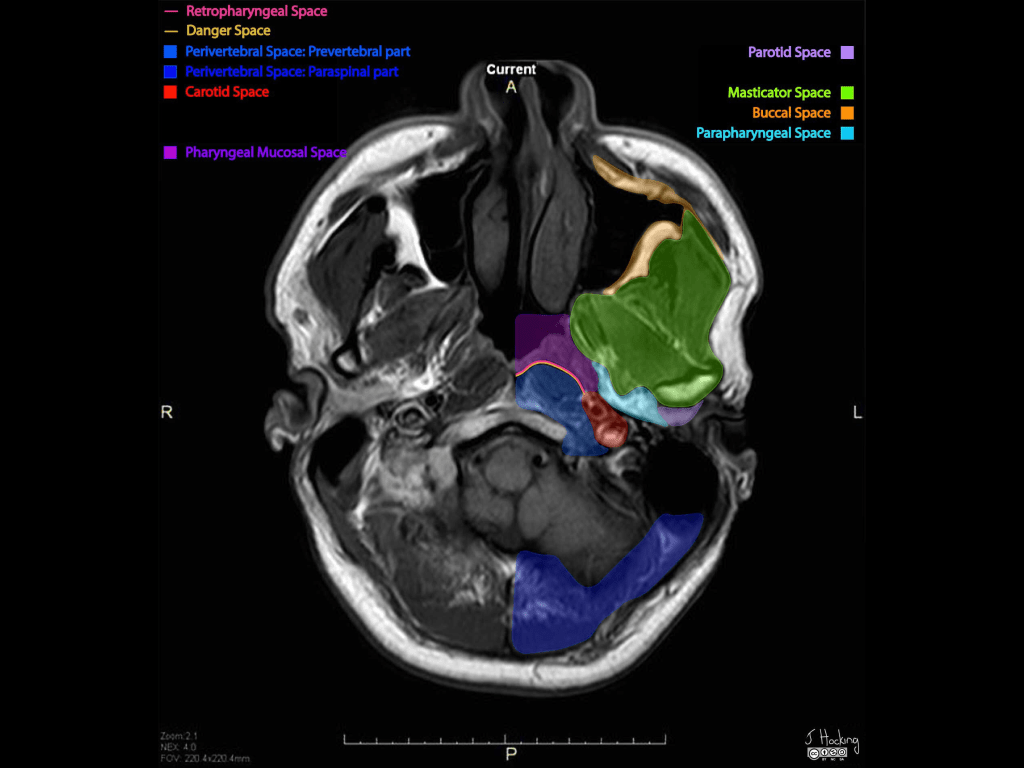

- Is one of the seven deep compartments of the head and neck

- Contents:

- Fat:

- Main component

- Deeps blood vessels:

- Internal maxillary artery

- Ascending pharyngeal artery

- Pterygoid venous plexus:

- Only small portion:

- Because it is mainly within:

- The masticator space

- Nerve:

- Small branch of the mandibular division of the trigeminal nerve (cranial nerve V):

- Supplying the tensor veli palatini muscle

- Salivary glands – depends on the definition:

- Some say that it contains no salivary glands, others

- Minor or ectopic salivary gland / rests

- Retromandibular portion of the deep lobe of parotid gland

- Lymph nodes

- Boundaries:

- The parapharyngeal space has complex fascial margins:

- Occupying the space between the muscles of mastication and the muscles of deglutition:

- Superior margin:

- Base of skull

- Inferior margin:

- Greater cornu of the hyoid bone:

- Although some state the space functionally ends higher:

- With the styloglossus muscle:

- At the level of the angle of the mandible

- Medial margin:

- Middle (pretracheal) layer of the deep cervical fascia:

- Covering the:

- Superior pharyngeal constrictor

- Levator palatini muscle and

- Tensor veli palatini muscle

- Lateral margin:

- Investing fascia (superficial layer) of the deep cervical fascia:

- Covering the deep lobe of the parotid

- Anterior margin:

- Covering the medial pterygoid muscle

- Posterior margin:

- Prevertebral layer of the deep cervical fascia

- Relations:

- Medial:

- To the masticator space

- Lateral:

- To the pharyngeal mucosal space

- Anterior:

- To the prevertebral space

- Posterior:

- To the medial pterygoid